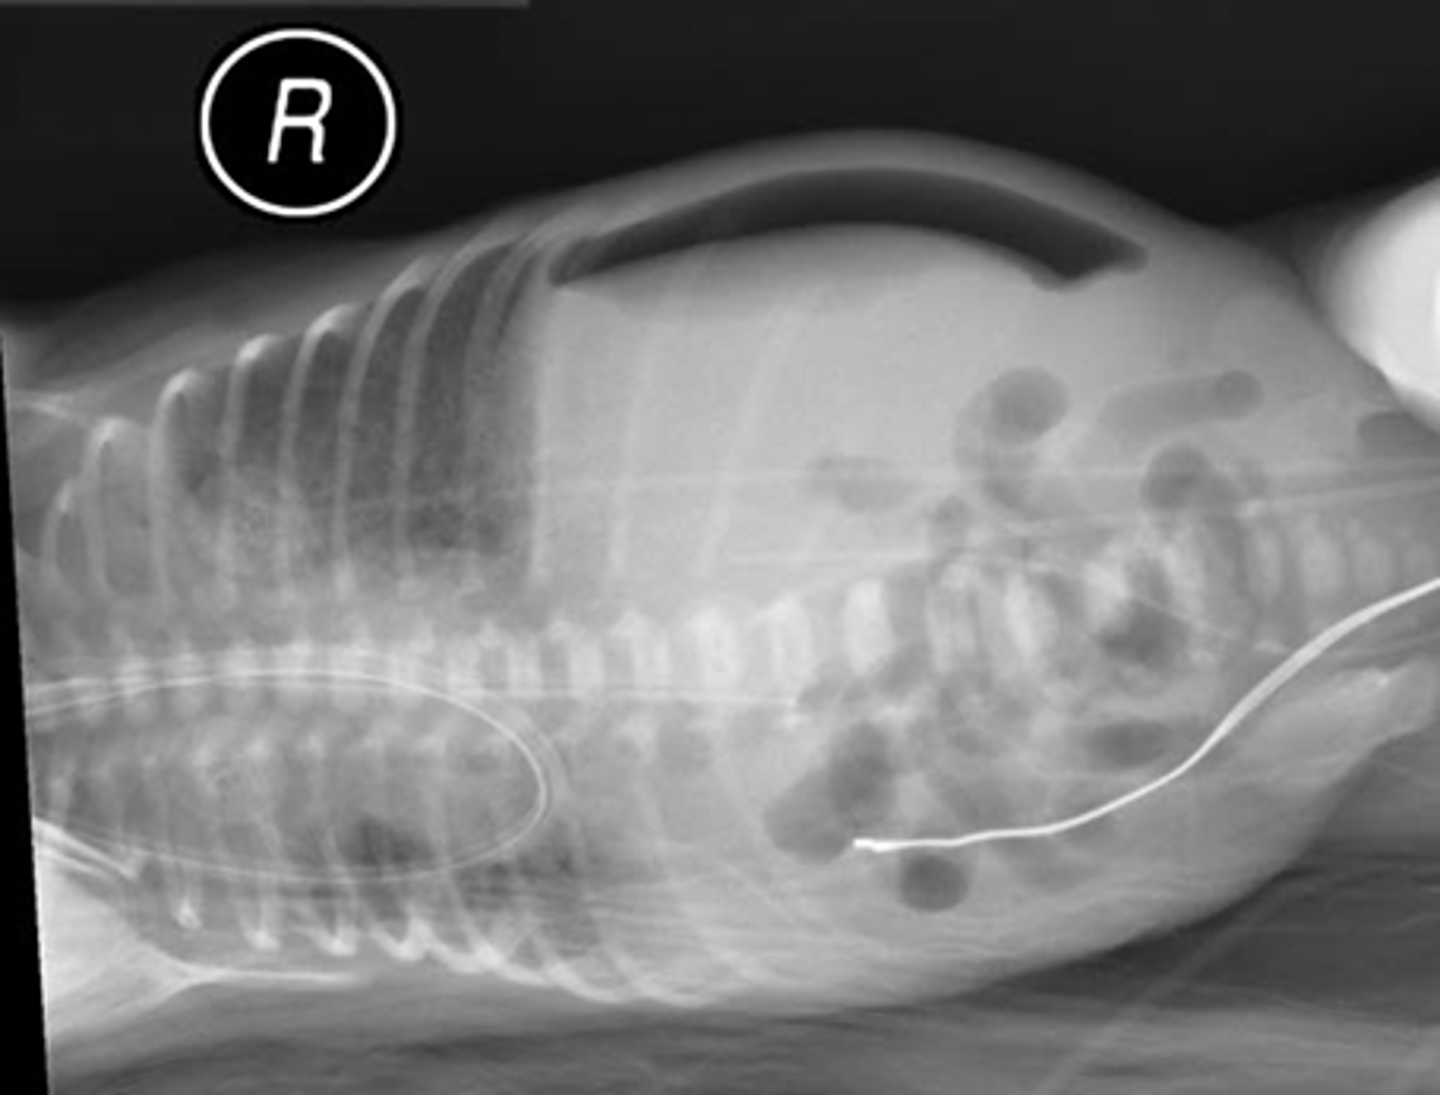

Pneumatosis - air in the abdominal wall.

WHITE ARROWS - RLQ demonstrating thin curvilinear lucency that parallels with the lumen of the adjacent bowel.

Appearance characteristic of gas in the bowel wall.

In infants the MC cause for this finding is necrotizing enterocolitis - a disease found mostly in premature infants in which the terminal ileum is most affected.

Pneumatosis intestinalis is pathognomonic for necrotizing enterocolitis in infants.